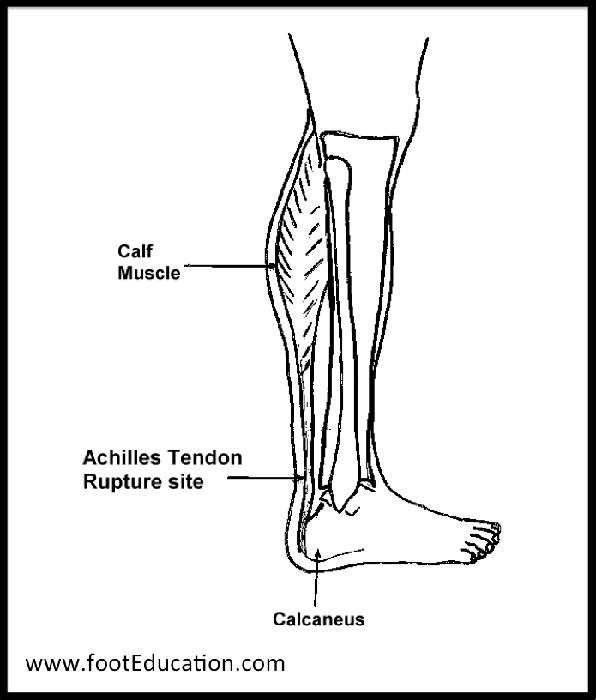

Achilles Tendon Rupture – FootEducation

Achilles Tendon Rupture stock illustration. Image of tear – 52456557

Achilles Tendon Rupture – Causes, Symptoms and Treatment | Bone and Spine